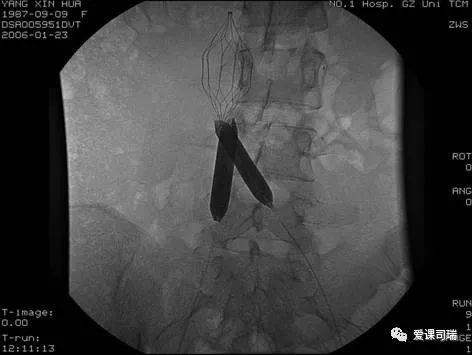

髂静脉闭塞介入开通后的球囊扩张成形